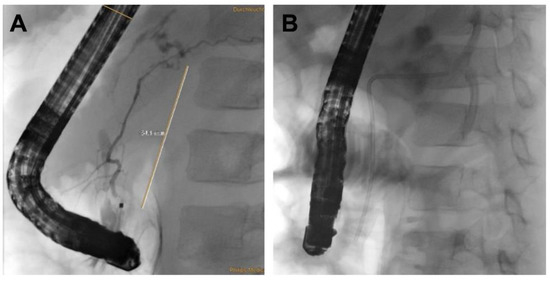

| Initial Management | Laparotomy, suture of the pancreatic head, distal pancreato-jejunostomy (Roux Y) | ERCP—complete dissection of the pancreas, Laparotomy, Jejunal repair, suture of the pancreatic head, distal pancreato-gastrostomy | ERCP—stenting of the ruptured pancreatic duct with 5 Ch pigtail drainage | ERCP unsuccessful, stenting of ruptured pancreatic duct not possible; chest drain (left side) |

| Management of complications | Anticoagulant therapy | - | Transgastric punction and drainage of pseudocyst with double-pig tail drain Ch 7, spontaneous dislocation of pig tail Antibiotic therapy Persistent fistula of the ruptured pancreatic duct, recurrent stenting (2 times), removal of stent after 5 months | Transgastric punction and drainage of pseudocyst with double-pig tail Ch 7, spontaneous dislocation of pig tail Antifungal therapy |